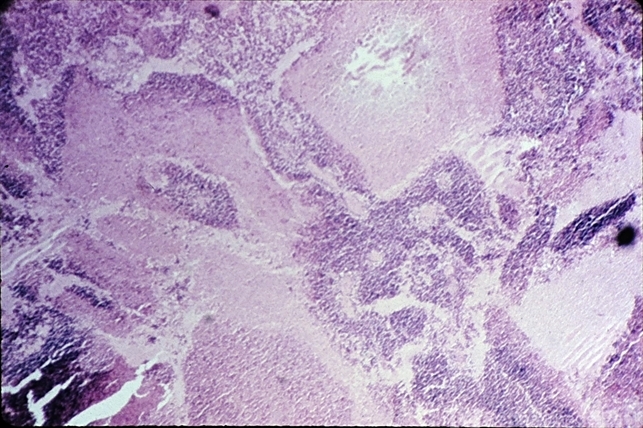

- Low-power view of a necrotic retinoblastoma with bands of darker, viable cells surrounding blood vessels ( x25).